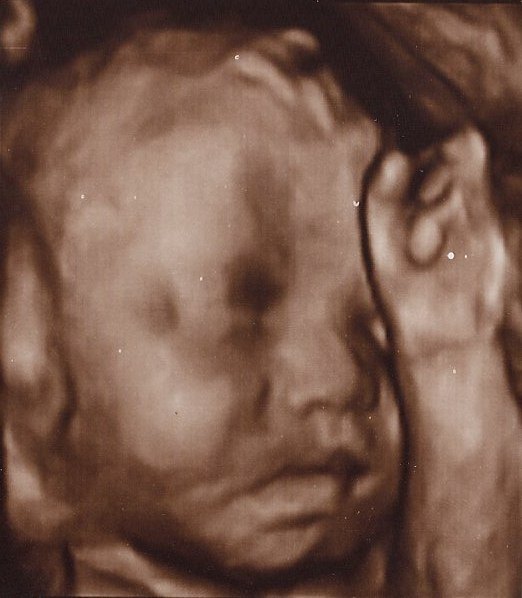

Det er så vildt at være til 3D scanning, det er som om, man er gravid på en helt anden måde bagefter

Ja, virkelig! Det er en hel anden måde at forholde sig til den lille på! Men når man ser billederne synes jeg man tænker "iih hun er stor", men hun er jo i virkeligheden stadig lillebitte. Lidt skægt